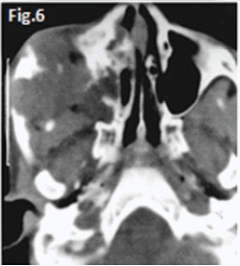

This 22 year old male patient (Figs.1 & 2) presented with a slow growing swelling in the left mandibular molar region. Figures 3, 4, 5 & 6 are images of three other patients with the same condition. Discuss the radiological features and what is your diagnosis?

Fig 1 & 2: the large lesion of left mandible shows a honeycomb-like distribution of calcifications. The borders are corticated. The tumour has displaced the mandibular molar tooth. A histological diagnosis of calcifying epithelial odontogenic tumour (Pindborg Tumour) was made. Fig.3 shows a Pindborg tumour distal to left second premolar associated with displacement of the first molar tooth. Fig.4 shows a similar tumour with mixed lucency-opacity between right premolar and molar teeth. Figs 5 & 6 show coronal and axial CT views of a large Pindborg tumour affecting the right maxilla. Note the marked expansion and cortical destruction. Calcifying epithelial odontogenic tumour is a rare benign neoplasm, accounting for less than 1% of all odontogenic tumours. The average age at diagnosis is 40 years; however, the tumour can occur at any age. It occurs equally in males and females. Approximately two thirds of cases are reported to occur in the mandible. Most cases occur in the premolar-molar area and are commonly associated with an unerupted tooth. The tumour is a painless, slowly enlarging mass. Histologically the tumour has a very characteristic appearance. Sheets of polyhedral cells with well-defined eosinophilic cytoplasm and hyperchromatic nuclei are featured. Amyloid and ringlike calcification may also be present. The tumour may be irregular or, in some cases, the cystic lesions may be well defined and corticated, whereas others appear ill defined. Small unilocular lesions may have a completely radiolucent centre (Fig.3). Others may have variable amounts of small flecks of calcifications scattered throughout. Larger lesions have a multilocular or honeycomb appearance. The tumour can displace and often prevent the eruption of teeth. Radiologically the tumour may be very similar to the calcifying odontogenic cyst, adenomatoid odontogenic tumour and ameloblastic fibro-odontoma.